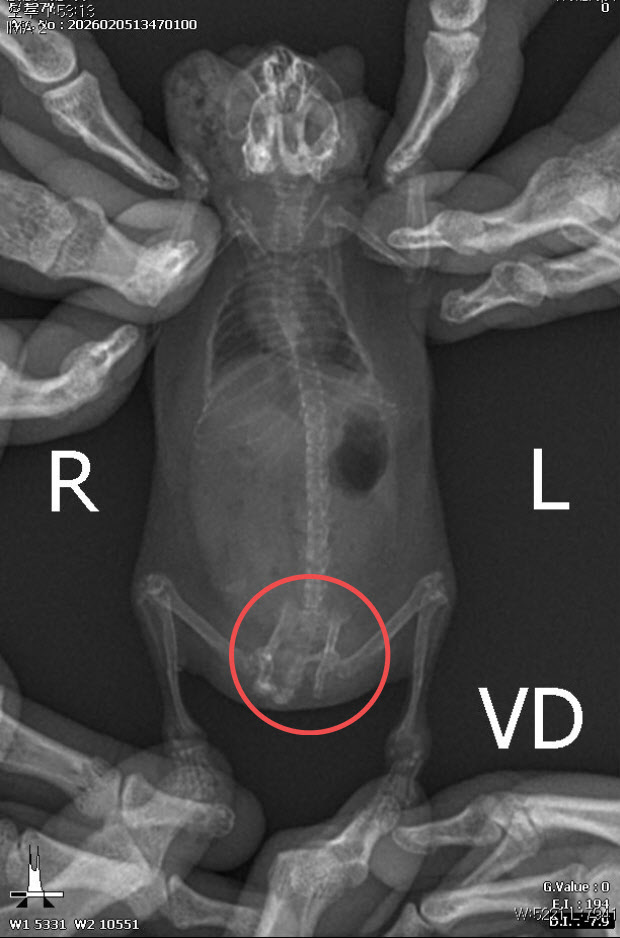

정글리안 햄스터의 골반이 골절된 흔적. (사진=동물자유연대 제공) |